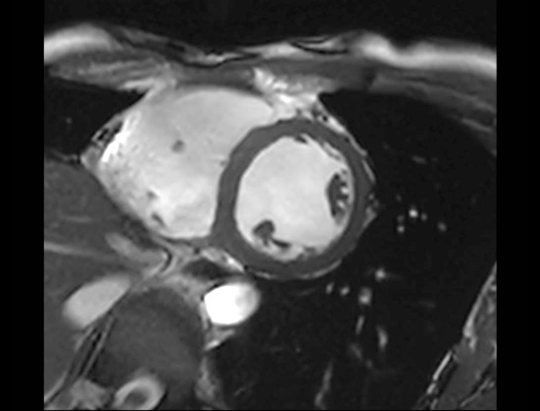

uMR Omega™는 타협 없이 MRI의 전통적인 한계를 넘어서는 것을 목표로 설계되었습니다. 이 혁신적인 75cm ultra-wide bore는 환자의 크기에 관계없이 사용될 수 있어, 환자의 상태를 더욱 효과적으로 관리할 수 있게 도와주며, 임상적인 정확도를 크게 향상시키고 임상 능력을 넓힐 수 있습니다. Ultra-wide bore는 미래를 내다보면서 단순히 독특하고 환자 중심의 경험을 제공할 뿐만 아니라, 방사선 치료 계획을 위한 MRI 시뮬레이션 또는 수술 중 MRI에도 큰 이점을 제공합니다.

Boundless Clinical Scenarios

uMR Omega™은 uAIFI 기술 플랫폼의 지원을 받아, 상당한 성능 향상, 강력한 이미징 능력, 개선된 작업 흐름 및 향상된 사용자 경험을 통해 많은 기대를 받고 있습니다.